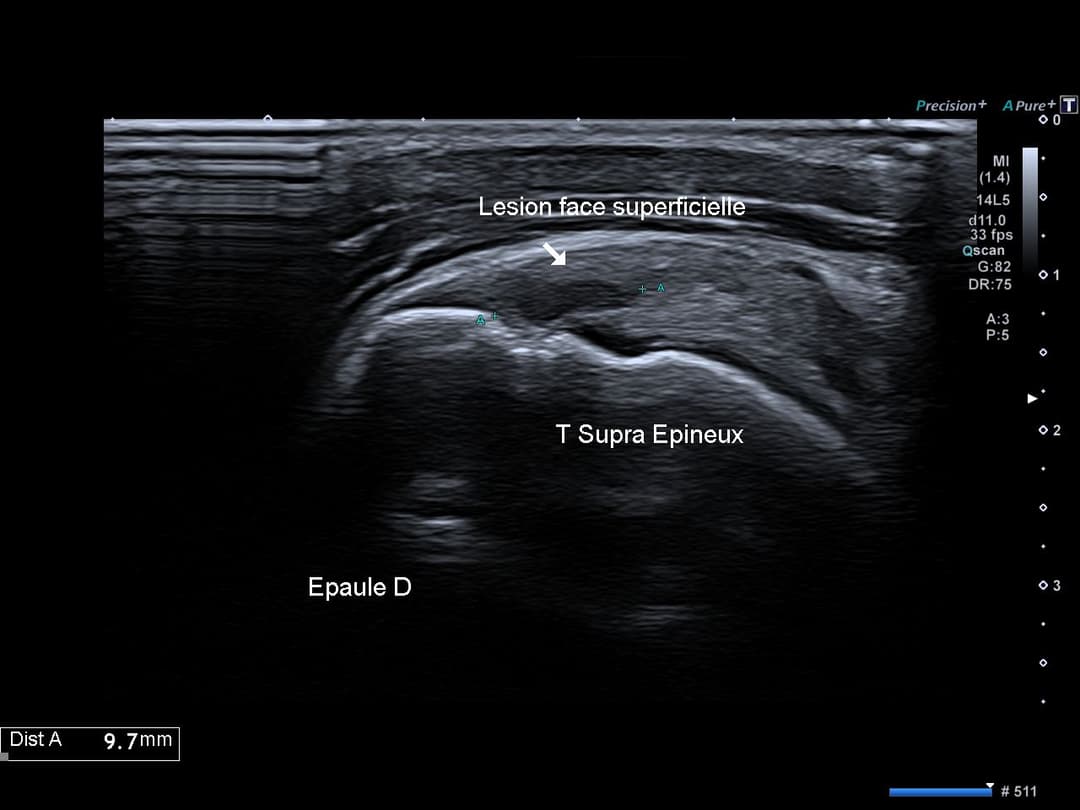

Perte de l'architecture habituelle à double corde du tendon supra épineux, désorganisation hypoéchogène de la face superficielle (bursale) du tendon supra épineux traduisant une rupture partielle.

Rupture de la face bursale du tendon supra épineux avec conservation de sa face articulaire

Rupture partielle du tendon supra épineux (face bursale)